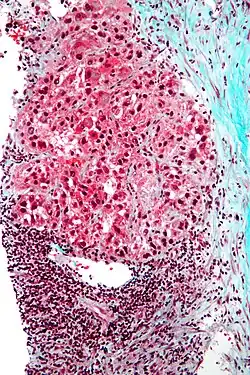

| Hepatocellular carcinoma in an individual who was hepatitis C positive; autopsy specimen | |